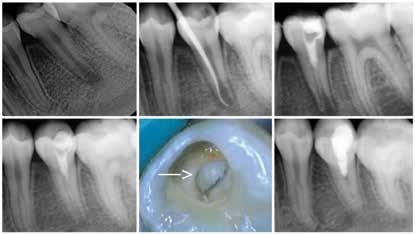

Magnetic resonance imaging (MRI) has been a staple in medicine and dentistry for many years. In dentistry, it serves a somewhat confined role in imaging the temporomandibular joints (TMJ) and occasionally the head and neck, including cysts or tumors. Dental MRI research and publications on these indications, as well as more “traditional” dental imaging tasks such as caries or periapical lesion detection, have progressed steadily since the mid-1980s, followed by a rapid increase in published papers in the early 2020s. These studies have long demonstrated the utility of MRI TMJ and cyst/tumor imaging, as well as the promise of MRI for essentially the entire range of dental imaging indications. Indications include caries, periapical disease, periodontal disease, growth and development/

The newly formed Orofacial MRI Center (OMRIC, dentistry.umn.edu/omric) at the University of Minnesota School of Dentistry is home to the first dental-dedicated MRI (ddMRI) unit in North America and the second installation of its kind in the world. Researchers Drs. Don Nixdorf and Laurence Gaalaas have an extensive track record in dental MRI research and development. Still, they are thrilled to have as an imaging tool one of the very first dental-dedicated MRI units, a Siemens MAGNETOM Free.

Max Dental Edition* MRI scanner. In collaboration with Dentsply Sirona and Siemens Healthineers, Nixdorf and Gaalaas secured a multi-year research agreement and constructed a physical imaging center around a Free.Max MRI unit. Beginning in early 2025, they initiated research studies to investigate the utility of ddMRI diagnosis in patients with endodontic, orthodontic and TMJ conditions. Such work will establish the utility of an experimental dedicated extraoral dental MRI coil and support proven indications for ddMRI imaging in endodontic, orthodontic, TMJ and other dental patient populations.

Proton density (left) and CBCT (right) images of apical lesion and furcation involvement at tooth #2. This tooth was clinically diagnosed with pulpal necrosis and a crack involving the furcation.

Proton density image showing improved image detail provided by dental dedicated MRI coil.